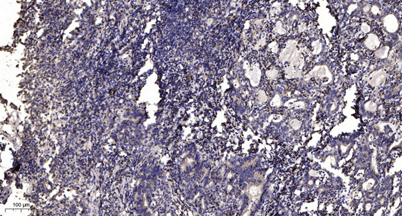

Applications IHC

Recomended Dilution IHC-p 1:50-300